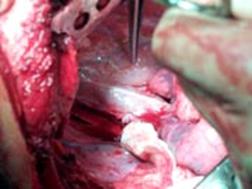

Leziune de pancreas Aspect dupa pancreatectomie distala